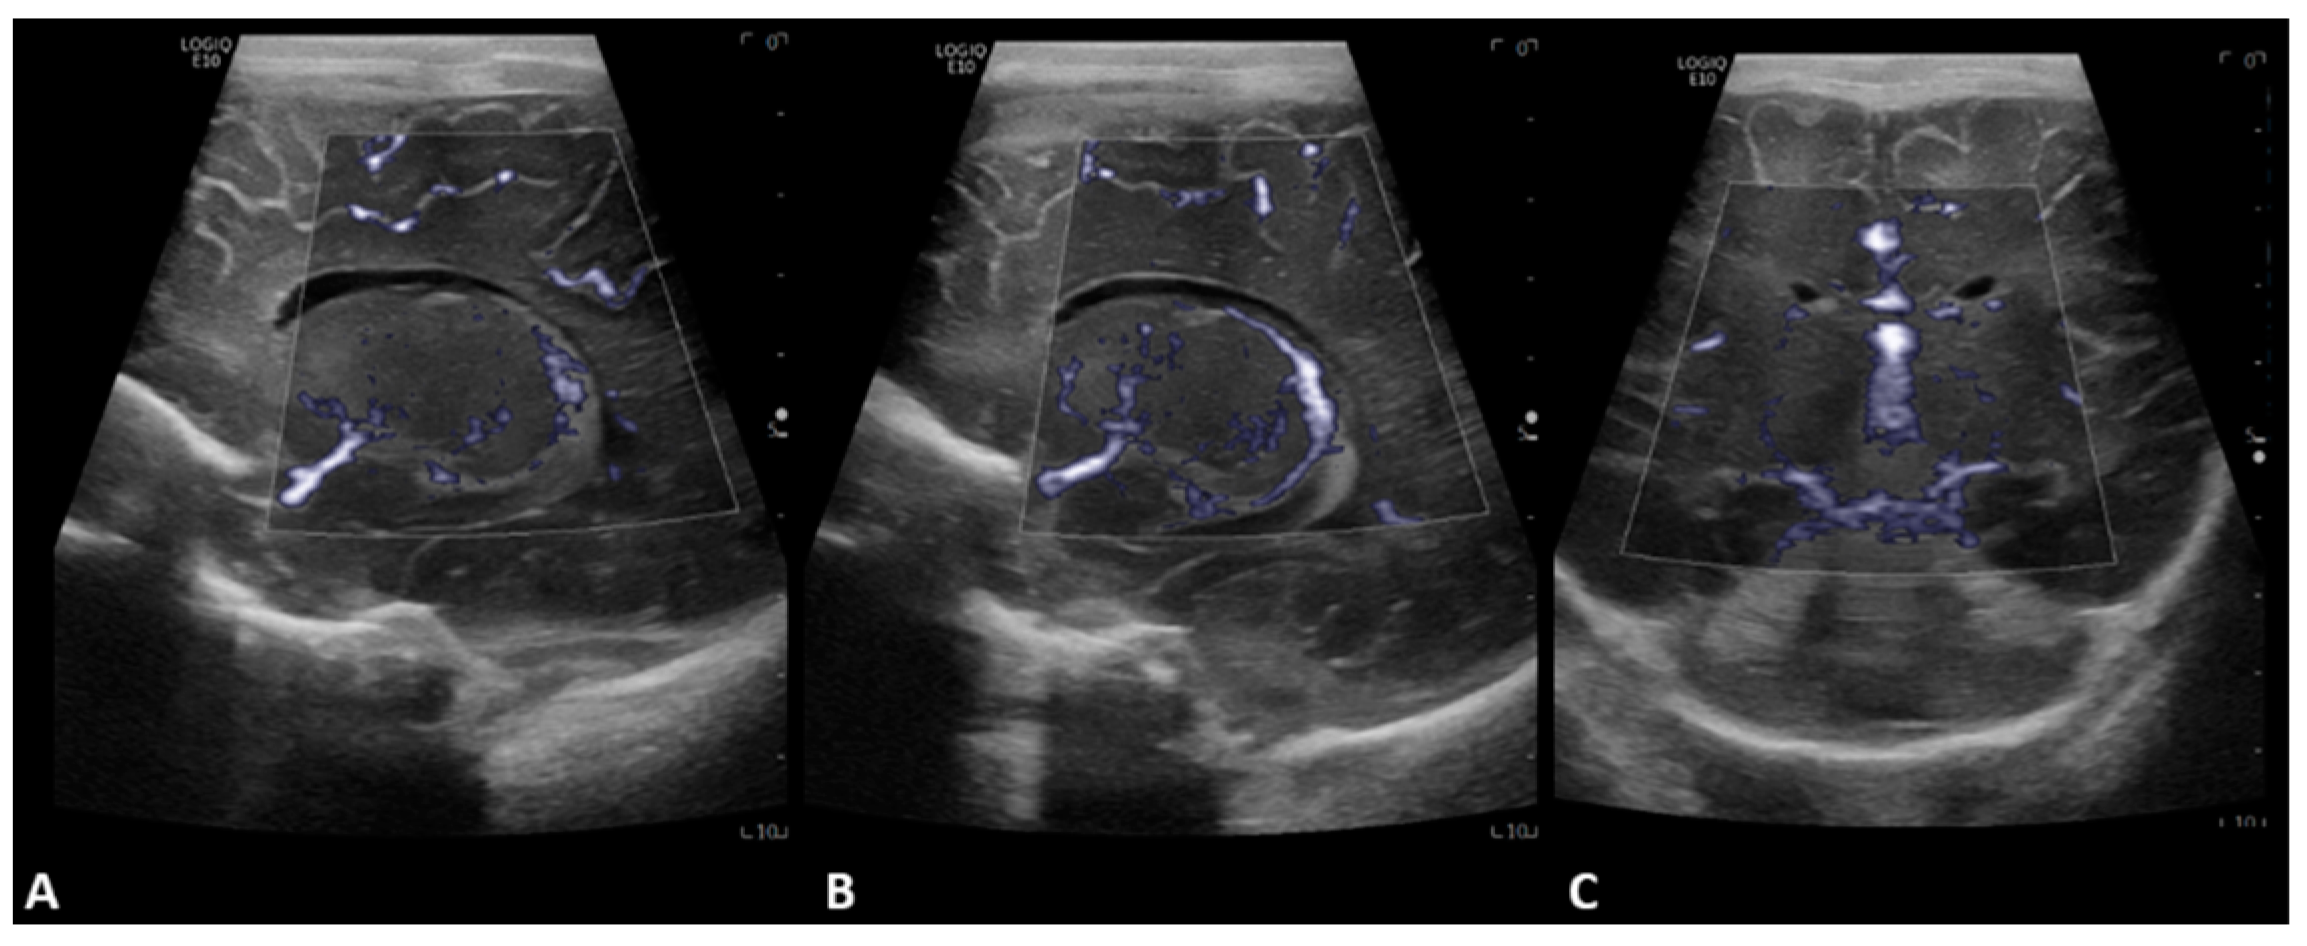

- Hwang, M.; Haddad, S.; Tierradentro-Garcia, L.O.; Alves, C.A.; Taylor, G.A.; Darge, K. Current understanding and future potential applications of cerebral microvascular imaging in infants. Br. J. Radiol. 2022, 95, 20211051. [Google Scholar] [CrossRef] [PubMed]

- Barletta, A.; Balbi, M.; Surace, A.; Caroli, A.; Radaelli, S.; Musto, F.; Saruggia, M.; Mangili, G.; Gerevini, S.; Sironi, S. Cerebral superb microvascular imaging in preterm neonates: In vivo evaluation of thalamic, striatal, and extrastriatal angioarchitecture. Neuroradiology 2021, 63, 1103–1112. [Google Scholar] [CrossRef]

- Goeral, K.; Hojreh, A.; Kasprian, G.; Klebermass-Schrehof, K.; Weber, M.; Mitter, C.; Berger, A.; Prayer, D.; Brugger, P.C.; Vergesslich-Rothschild, K.; et al. Microvessel ultrasound of neonatal brain parenchyma: Feasibility, reproducibility, and normal imaging features by superb microvascular imaging (SMI). Eur. Radiol. 2019, 29, 2127–2136. [Google Scholar] [CrossRef] [PubMed]